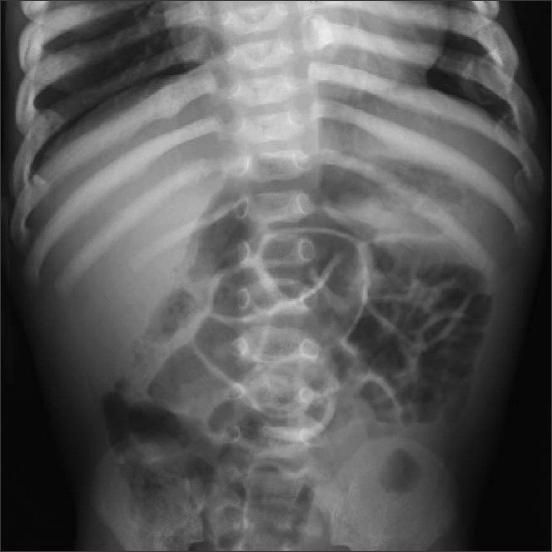

This image was obtained from a 5-month-old boy who was brought to the emergency department (ED) by his parents who noted new-onset rectal prolapse. The prolapse had promptly recurred following initial successful reduction under sedation in the ED. A surgical consultation was obtained, and abdominal radiographs were requested.

What diagnostic clues do you read in these images?